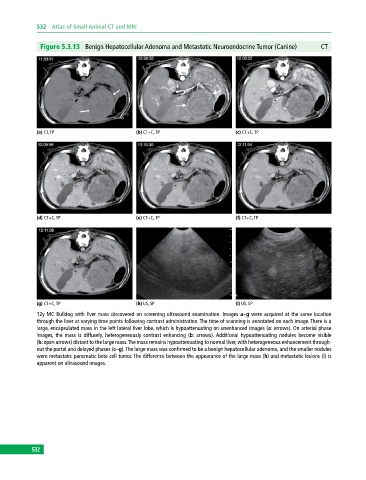

Figure 5.3.13 Benign Hepatocellular Adenoma and Metastatic Neuroendocrine Tumor (Canine) CT

12y MC Bulldog with liver mass discovered on screening ultrasound examination. Images a–g were acquired at the same location

through the liver at varying time points following contrast administration. The time of scanning is annotated on each image. There is a

large, encapsulated mass in the left lateral liver lobe, which is hypoattenuating on unenhanced images (a: arrows). On arterial phase

images, the mass is diffusely, heterogeneously contrast enhancing (b: arrows). Additional hypoattenuating nodules become visible

(b: open arrows) distant to the large mass. The mass remains hypoattenuating to normal liver, with heterogeneous enhancement through-

out the portal and delayed phases (c–g). The large mass was confirmed to be a benign hepatocellular adenoma, and the smaller nodules

were metastatic pancreatic beta cell tumor. The difference between the appearance of the large mass (h) and metastatic lesions (i) is

apparent on ultrasound images.